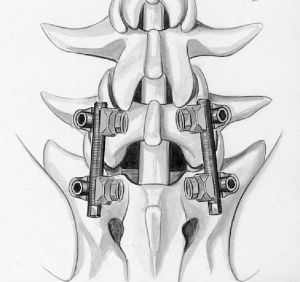

Хирургическое лечение спондилолистеза заключается в фиксации «разболтанных» позвонков титановыми винтами. Винты вводятся в позвонки через дужки позвонков (с лат. «педикули»), поэтому такая фиксация называется «транспедикулярной». Данный метод фиксации позвонков был впервые применен Roy-Camille в 1963г. и используется благодаря своей высокой эффективности по всему миру до настоящих дней.

Кроме того, в зависимости от техники проведения операции могут использоваться межтеловые кейджи. Кейдж (в переводе с английского «cage» означает «сетка») представляет собой титановый или пластиковый имплант, заполняемый собственной костной крошкой пациента или другим остеоиндуктивным (костьобразующим) материалом. Кейджи устанавливаются в полость диска, в результате чего восстанавливается высота последнего и соответственно высота фораминального отверстия (через который выходит спинномозговой корешок из позвоночного канала). Кейджи могут быть цилиндрической или прямоугольной формы, выполненными из титана или «PEEK»-керамики. Титановые цилиндрические кейджи в настоящее время используются редко.

Наиболее современным методом фиксации в настоящий момент является миниинвазивная технология введения винтов через небольшие разрезы. Этот метод позволяет меньше травмировать мышцы разгибатели позвоночника при введении винтов, а также более быстрому выздоровлению пациента и возвращению к обычному образу жизни, активному отдыху и работе. Технология данной фиксации заключается в использовании канюлированных винтов, т.е. винтов с отверстием в центре. В начале в тело позвонка вводится спица, а уже по спице вводится винт. Удаление грыжи диска и введение кейджа в межтеловой промежуток производится через тот же разрез, что и введение винтов.